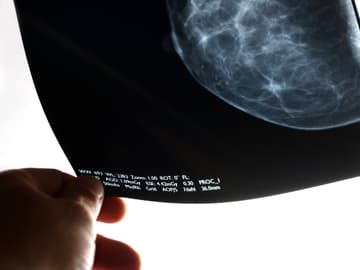

Digitale Mammografie: Wie ein Film

Die Patientinnen werden keinen Unterschied zur bisherigen 2D-Technik bemerken. Das Gerät nimmt eine Reihe von Röntgenbildern auf, jedes aus einer anderen Richtung. Diese millimeterdünnen Schnittbilder werden dann zu einer 3D-Präsentation zusammengesetzt. Auf dem Monitor kann man sich durch die Schichten scrollen, das ist wie ein Film, in dem man sich das Brustgewebe anschauen kann.